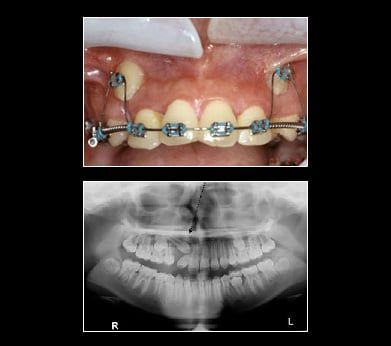

Treatment for Impacted Canines

After assessing your situation, Fresh Smile Dental Practice will devise a plan to make room for your canines. With a typical oral surgery and the assistance of an orthodontist your canine will find their way into their proper place over time.